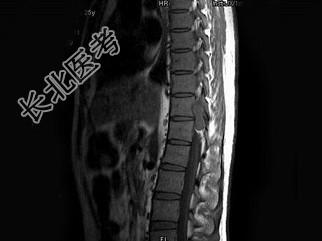

- 单项选择题男,25岁, 慢性腰痛伴间歇性跌倒半年,双下肢无力不能行走1月, MRI见下胸段椎管内肿瘤呈“哑铃”状应诊断为 ( )